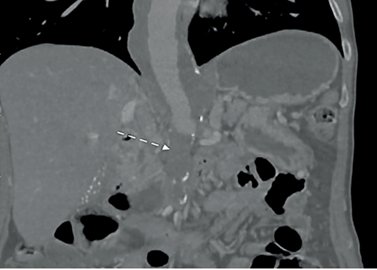

Se abordó inicialmente como posible patología aórtica aguda, con indicación de monitoreo invasivo en unidad de cuidado intensivo (UCI) con soporte con labetalol en infusión continua, con control de cifras tensionales sistólica por debajo de 120 mmHg. Se realizó de carácter emergente tomografía computarizada con protocolo de aorta, en la cual se documentó aneurisma de aorta toracoabdominal Crawford IV de 38x39 mm con oclusión aorto-ilíaca TASC D y oclusión crónica del TC y AMS, con recanalización en el tercio medio de esta última (Figura 1).